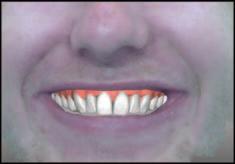

A unilateral sagittal split osteotomy was performed using piezosurgery to protect the nerve. The alveolar nerve, extending from the apical region of the left first and second molars to the mental foramen, was uncovered, and a meticulous dissection was performed to release it from the canal. Notably, rigid paste debris was observed in proximity to and within the nerve canal. The nerve exhibited signs of swelling and was surrounded by granulation tissue (Figures 4 and 5 ).

FIGURE 4: Unilateral sagittal split osteotomy.